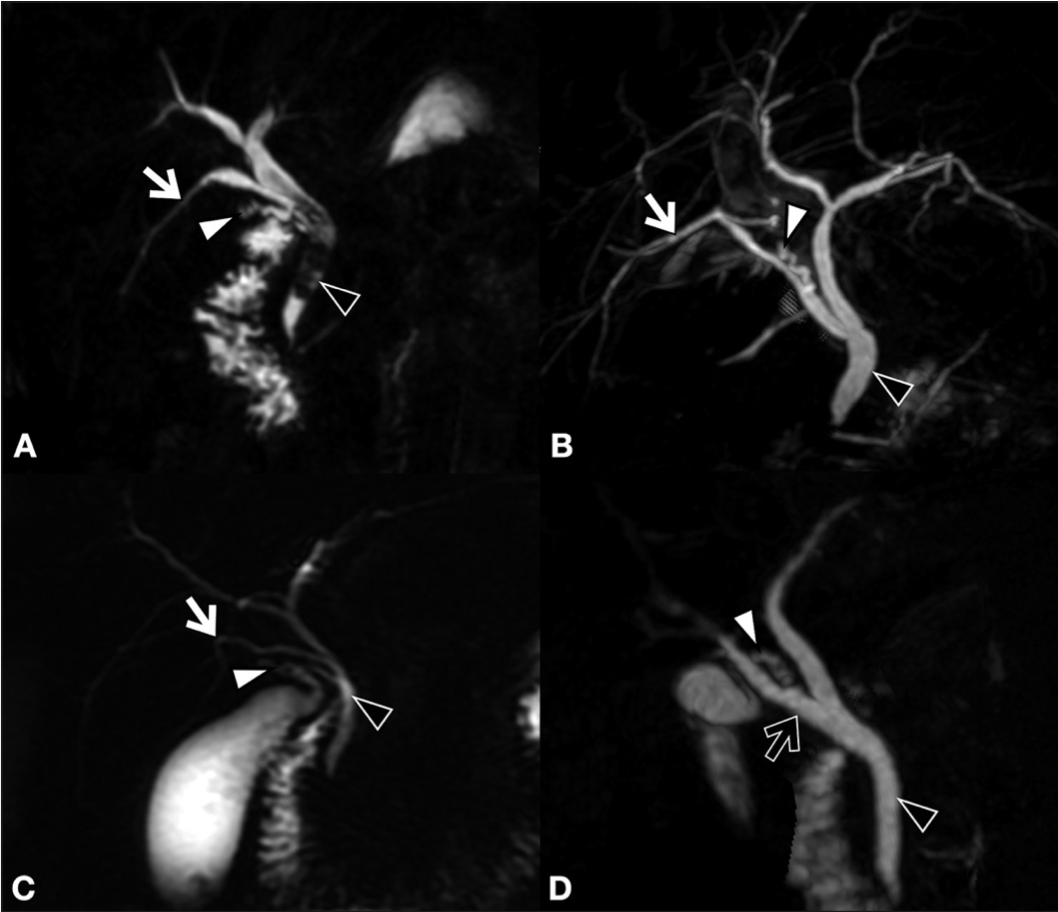

La finalidad de esta revisión es mostrar el estado actual de las lesiones de vía biliar (LVB), producidas especialmente durante la colecistectomía laparoscópica. Revisaremos la etiopatogenia, los grados de compromiso biliar, las lesiones vasculares asociadas, las clasificaciones utilizadas y los factores de riesgo. Además la forma como evaluar oportunamente la magnitud de la lesión, tanto en la misma cirugía como en el postoperatorio. Igualmente se muestran las diversas alternativas terapéuticas empleadas. Todo con la finalidad de evitar graves complicaciones.